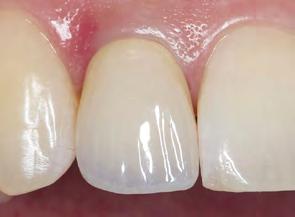

Estudios tomográficos en los cuales se observa tumoración expansiva a piso nasal de 3 centímetros de diá metro aproximadamente isodensa a tejidos blandos en zona de pala dar blando (Figura 3A y 3B). Motivo por el cual se decidió realizar biopsia incisional (Figura 4A , 4B y 4C) obte niendo un diagnóstico de Adenocar cinoma de células basales en paladar blando (Figura 5) con el cual se rea lizó referencia al centro oncológico naval para su seguimiento y trata miento. Actualmente se encuentra en tratamiento de quimioterapia.

Figura 5. Proliferación neoplásica de estirpe epitelial, morfología predominantemente basaloide. A B